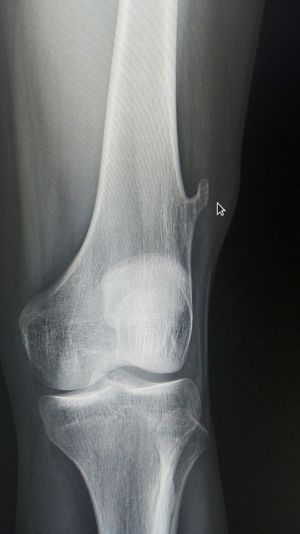

Xray

Knee

Exostosis